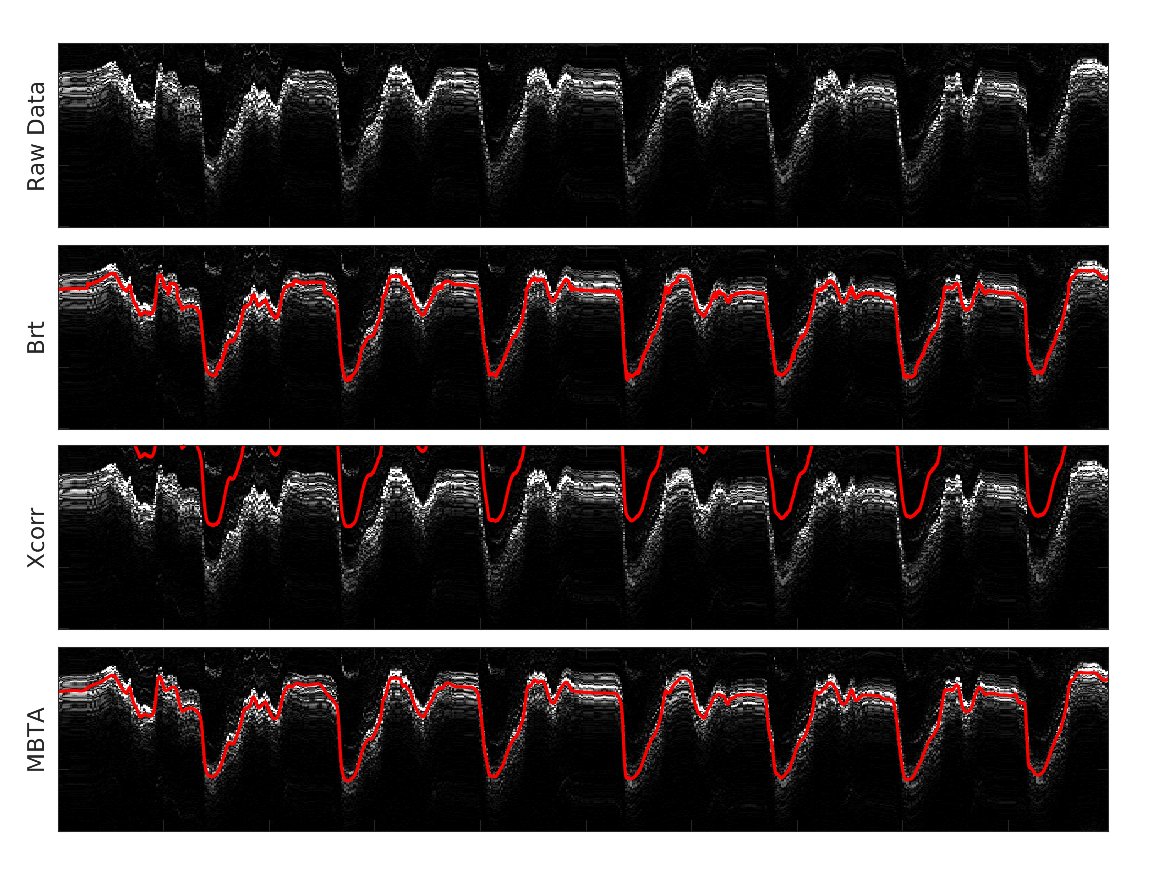

1. A模式超声技术

A模式超声技术是一种通过测量超声波在组织中传播的速度和时间来评估组织特性的方法。在本研究中,我们采用单元件超声换能器,通过连续发送超声波并接收反射信号,实时跟踪肌肉厚度的变化。

1. 受控等速收缩实验结果

在受控等速收缩实验中,我们发现肌肉厚度变化与关节扭矩之间具有良好的相关性。通过建立的数学模型,我们在肘部和膝盖的扭矩估计中实现了小于7.6%的误差,决定系数(R²)大于0.92。

2. 动态现实任务实验结果

在动态现实任务中,可穿戴A模式超声设备成功地实时记录了肌肉厚度变化,并估计了关节扭矩。尽管动态活动中的肌肉活动模式更为复杂,但我们的方法仍然能够在举重、骑自行车、跑步机运动和室外运动等任务中提供可靠的关节扭矩估计。